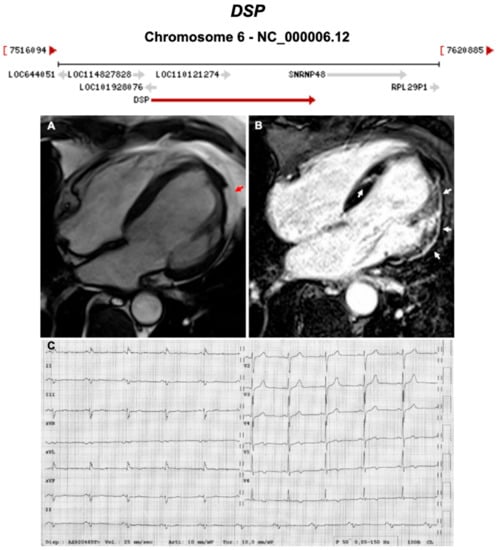

3.1. Desmosomal Genes

| DSP | Desmosome | 1–13% | AD | LV, BIV | ARVC8 | 6p24.3; 24 | Cardiocutaneous Syndrome AR (Carvajal), can also have cardiocutaneous with AD | Definitive for ARVC |